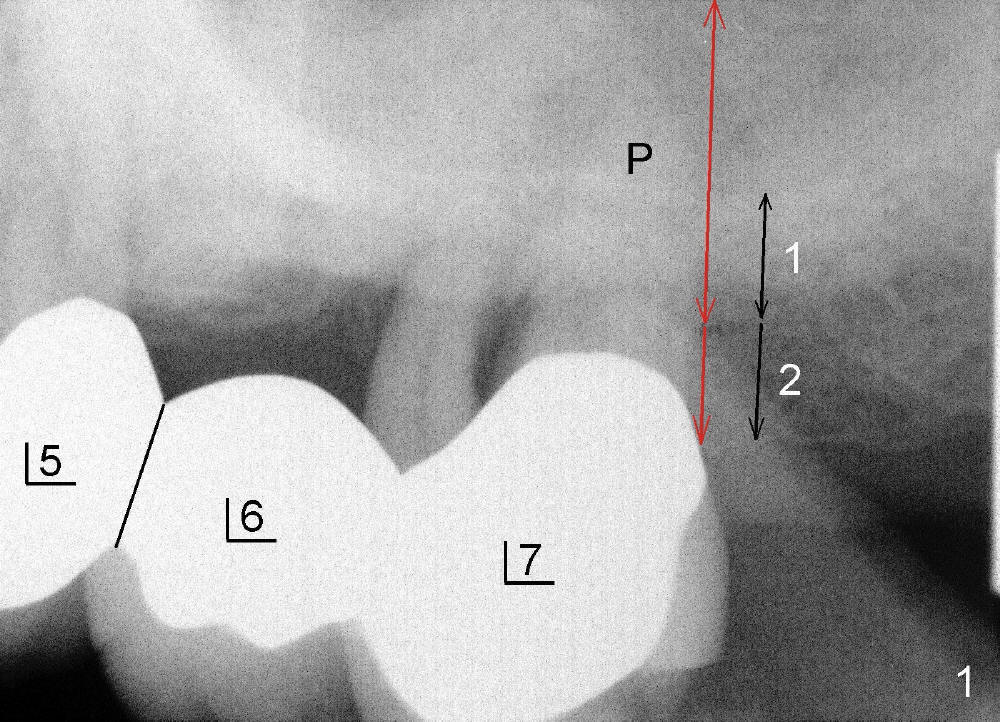

分析上颌骨牙槽嵴高度有一定难度,主要是因为上颌窦,它的底板在这个病例特别白(图一:黑箭头(1)),好像这就是牙槽嵴高度,其实第一部分下面有骨质比较疏松部分(2),所以初步看:牙槽嵴高度至少1加2(黑箭头)。但是左上七牙根尤其是鄂侧根(P)不是空空地伸入上颌窦,它的根尖周围还有阴影,阴影上面可能还有骨皮质,所以能与种植体接触的骨头高度应该是图一两个红箭头总和,这就相当可观了。初步设计显示我们可以植入七乘十七毫米种植体(图二),其中三毫米(长度)与牙龈接触。

首先在左上五,六号牙之间切断牙桥(图一:黑线),七号基牙比五号松,前者鄂侧牙周袋深,所以对七号牙大刀阔斧,不幸远中颊侧根断裂(图三:离体牙颊侧观;MB:近中颊侧根),可能因为根弯曲,或者死髓牙。图四是离体牙近中观:把断根(远中颊侧根:DB)插回原处,试图把种植体植入三个牙根之间中隔(septum),不过最后种植体主要进入鄂侧根牙槽窝。综合使用骨凿,钻头(图五:D;四点五乘十七毫米)和taps形成植牙窝,当四点五乘十七毫米tap进入植牙窝十四毫米左右,它不稳定,它一定要再深入三个毫米时,才牢靠,似乎非要卡在上颌窦底板最上缘骨皮质中不可。这个现象同样发生在较大taps使用过程中(例如五乘十七,六乘十七,七乘十七毫米)。当七乘十七毫米锥形种植体旋入时(图六:I:植牙;C:喙突),扭力大于六十Ncm。